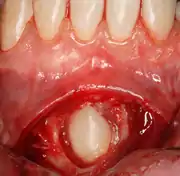

Pericoronitis

Pericoronitis is an infection of the soft tissue that covers the crown of an impacted tooth and is usually caused by the normal oral microbiota. For most people there exists a balance between the host defenses and the oral micriobiota but if the host defenses are compromised like during minor illness such as influenza or an upper respiratory tract infection, pericoronitis results. Another common cause is entrapment of food beneath the gum flap (also called an operculum). Pericoronitis can present as a mild infection or severe infection. In its mildest form it is just a localized tissue swelling and soreness whereas in severe forms the swelling is slightly larger even sometimes creating trismus (difficulty opening the mouth).

In some cases, for aesthetic purposes, a surgeon may wish to expose the canine. This may be achieved through open or closed exposure. Studies show no advantage of one method over another.[11]